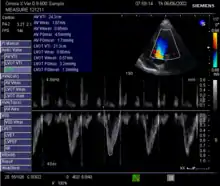

Echocardiography

Echocardiography is a non-invasive method of quantifying cardiac output using ultrasound. Two-dimensional (2D) ultrasound and Doppler measurements are used together to calculate cardiac output. 2D measurement of the diameter (d) of the aortic annulus allows calculation of the flow cross-sectional area (CSA), which is then multiplied by the VTI of the Doppler flow profile across the aortic valve to determine the flow volume per beat (stroke volume, SV). The result is then multiplied by the heart rate (HR) to obtain cardiac output. Although used in clinical medicine, it has a wide test-retest variability.[8] It is said to require extensive training and skill, but the exact steps needed to achieve clinically adequate precision have never been disclosed. 2D measurement of the aortic valve diameter is one source of noise; others are beat-to-beat variation in stroke volume and subtle differences in probe position. An alternative that is not necessarily more reproducible is the measurement of the pulmonary valve to calculate right-sided CO. Although it is in wide general use, the technique is time-consuming and is limited by the reproducibility of its component elements. In the manner used in clinical practice, precision of SV and CO is of the order of ±20%.